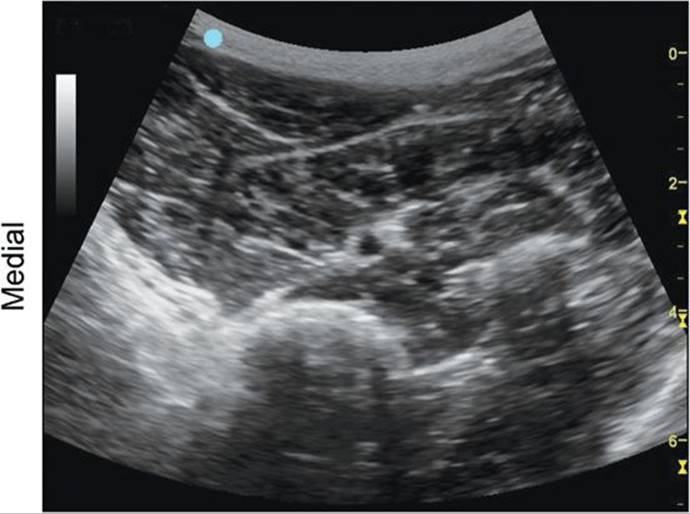

Posterior Tibial Nerve at the Ankle, Medial Aspect

FIGURE 7.59.1A Ultrasound transducer position to image the posterior tibial nerve at the ankle, medial aspect.

FIGURE 7.59.1B Ultrasound image of the posterior tibial nerve at the ankle, medial aspect.

FIGURE 7.59.1C Labeled ultrasound image of the posterior tibial nerve at the ankle, medial aspect.

FIGURE 7.59.1D Labeled cross-sectional anatomy of the peroneal nerve, deep and superficial branches at the level of the ankle.

Abbreviations: PTN, Posterior Tibial Nerve; PTA, Posterior Tibial Artery; PTV, Posterior Tibial Vein; Med. Mall., Medial Malleolus.